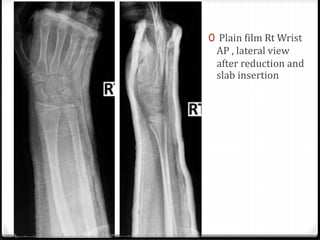

0 Plain film Rt Wrist

AP , lateral view

after reduction and

slab insertion

0 Closed reduction with short arm AP slab

and arm sling